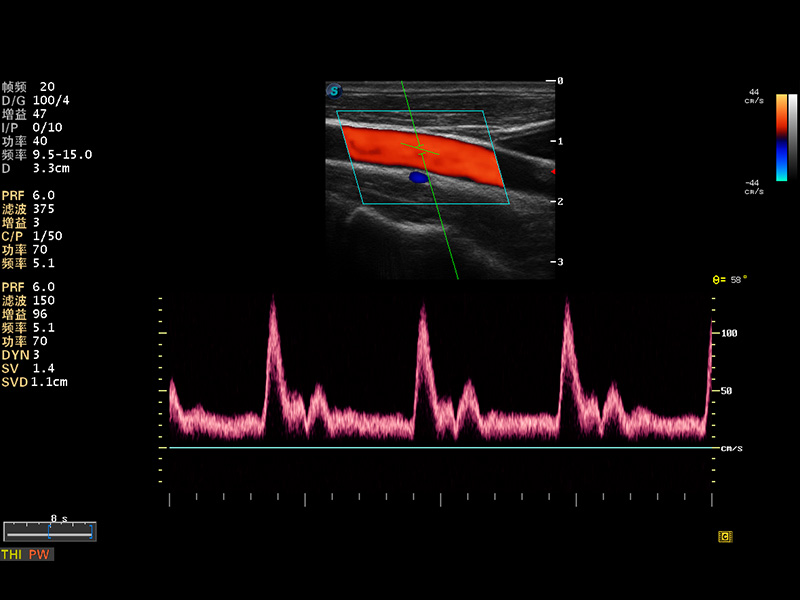

S8 EXP便携式彩色多普勒超声诊断仪是环球UG官网研发的高端全身应用型便携彩超。高通道的VIS平台融合可视化(Visual)、智能化(Intelligent)和人性化(Smart)的特点,配以环球UG官网自主研发生产的探头大家族,使您能够快速、准确的获得病人信息,提高工作效率的同时减轻疲劳。

成像技术

多波束形成器

μ-Scan微米成像

谐波成像

实时宽景成像

空间复合成像